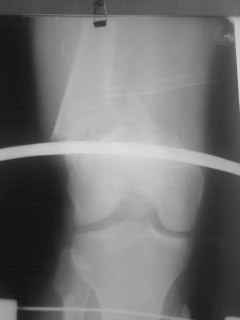

01.12.09г. оперировал больного с подобной травмой в ЦРБ на 4-е сутки после ДТП. Перелом открытый - рана находилась медиально чуть выше надколенника длиной примерно 3-4 см. До этого при поступлении было выполнено ПХО раны и скелетное вытяжение. На момент операции рана без признаков воспаления, состояние больного удовлетворительное.На первичных снимках перелом А3. На операции оказалось С3. Перелом фиксирован мыщелковой пластиной. Для репозиции понадобился медиальный доступ. Медиальный блок дополнен костно-губчатым аутотрансплантатом. На сегодняшний день раны заживают первично, швы еще не сняты, температура тела нормальная, отек бедра значительно уменьшился, имеется анемия средней степени, проводится ЛФК. Фото досылаю